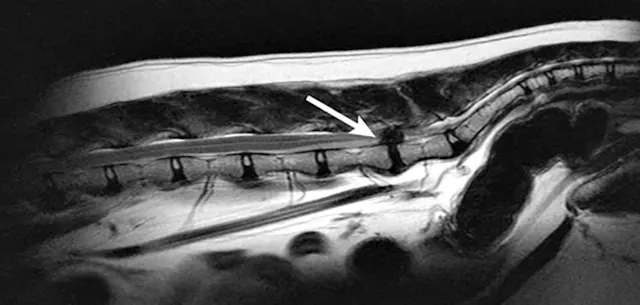

MRI is the diagnostic procedure of choice because it can identify soft tissue (eg, cauda equina, epidural fat, intervertebral disk) at the lumbosacral region without use of contrast (Figures 4 and 5).